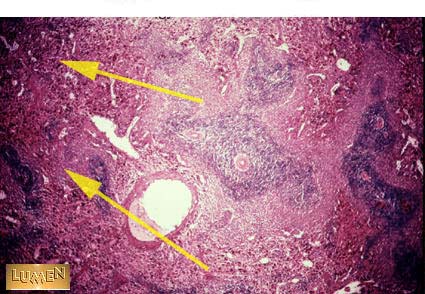

QA What is this region of the spleen called?

QB Why?

REd Pulp

contains sinusoids

and hematopoietic

tissus